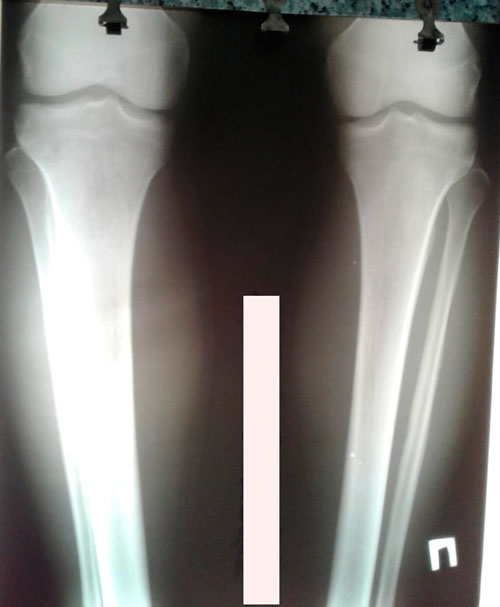

Исходник - 35 лет.

Дата операции -29.04.2019г.

рентген в 60 дней.

Рентген делаем всегда с коленным суставом!!!